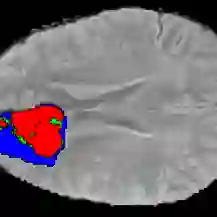

Current research on deep learning for medical image segmentation exposes their limitations in learning either global semantic information or local contextual information. To tackle these issues, a novel network named SegTransVAE is proposed in this paper. SegTransVAE is built upon encoder-decoder architecture, exploiting transformer with the variational autoencoder (VAE) branch to the network to reconstruct the input images jointly with segmentation. To the best of our knowledge, this is the first method combining the success of CNN, transformer, and VAE. Evaluation on various recently introduced datasets shows that SegTransVAE outperforms previous methods in Dice Score and $95\%$-Haudorff Distance while having comparable inference time to a simple CNN-based architecture network. The source code is available at: https://github.com/itruonghai/SegTransVAE.